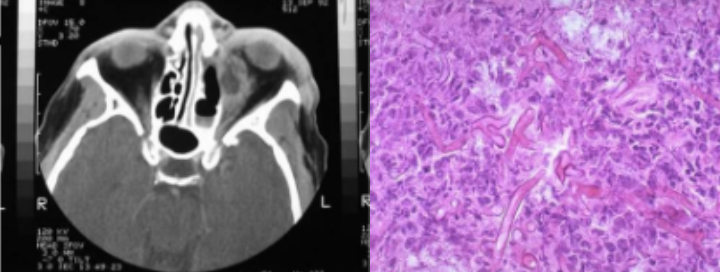

4b. Carcinoma of maxillary sinus

Clinical Features

Patients may have symptoms of sinusitis or referred pain to teeth

may cause malocclusion or mobile teeth

may appear as ulcerated mass in palate or alveolus

Cause

Unknown; some occur in woodworkers

Significance

Prognosis only fair; metastasis are not common

Intraoral ulceoproliferative growth involving the palate

Orthopantomography showing a soft tissue shadow in the left palate region

Computed tomography of the orofacial region showing heterogenous enhancement in the left maxillary sinus and destruction of the palate and left maxillary antrum